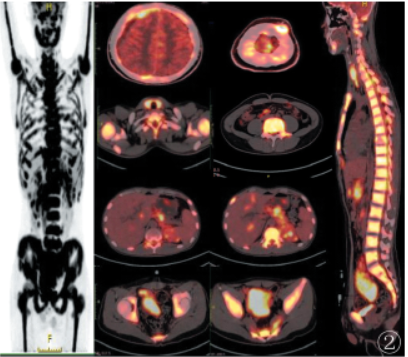

。PET-CT(图2)示:盆腔糖代谢异常增高软组织肿块,最大截面约7.3cm×5.7cm,SUVmax=13.6,双肾、左侧肾上腺、胃壁、甲状腺、胰腺、肝脏多发糖代谢摄取异常增高的病变,SUVmax分别为7.9、8.4、5.3、11.2、10.3、10.5;全身骨骼弥漫性糖代谢摄取异常增高,SUVmax=11.2,不伴有明显骨质破坏征象;双侧额颞顶部脑膜增厚伴糖代谢增高,SUVmax=10.2,右侧额颞顶部硬膜下积液;左侧顶部皮下糖代谢异常增高结节,约1.2cm×1.5cm,SUVmax=13.7;右下腹部分肠管增厚伴糖代谢异常增高,近端肠管未见梗阻,SUVmax=11.2;左颈部、前上纵膈、腹膜后糖代谢增高淋巴结,大者约1.0cm×0.9cm,SUVmax=8.0。

图2PET-CT示:双肾、左侧肾上腺、胃壁、甲状腺、胰腺、肝脏多发糖代谢异常增高灶;全身骨骼弥漫性糖代谢异常增高;右下腹部分肠管增厚伴糖代谢异常增高;盆腔巨大糖代谢异常增高软组织肿块;双侧额颞顶部脑膜增厚伴糖代谢增高;腹膜后糖代谢增高淋巴结,左侧顶部皮下糖代谢异常增高结节

结合患者年龄比较小,全身侵犯严重,且全身病灶未见明显坏死,肠管增厚但未出现梗阻症状,考虑淋巴瘤,结外淋巴瘤(ENL)可能大,建议活检。随后患者根据PET-CT检查结果行胃镜检查